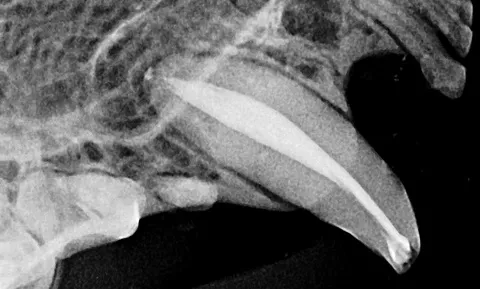

Fig. 2: X-ray showing a cat’s exposed root canal before therapy.

Fig. 3: X-ray showing a cat’s root canal after therapy; the root is filled and the crown is restored.